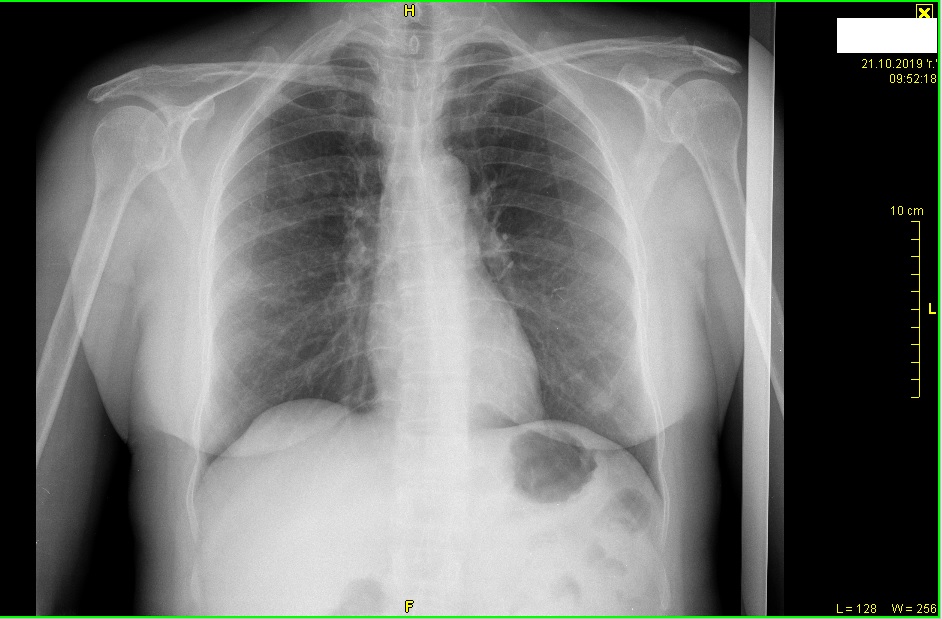

Здравейте, преди около месец на майка ми и правиха скенер на прешлени и гръбначен стълб, относно шум в ушите (който е от няколко месеа и не се повлиява от лекарства) със съмнение за ошипяване, лекарят, който е разчел резултатите от скенера и казал, че се вижда нещо на белия дроб и е добре да се обърне към пулмолог, за да и направи допълнителни изследвания. Свързахме се с лекар пулмолог, но тя не прегледа скенера, а само я прослуша и я изпрати на рентген, където не се видя нищо, което е според мен е логично, защото доколкото разбирам от скенера той е правен в профил, а рентгенографията в анфас, моля за Вашето мнение, относно снимките от скенера и тази от рентгена.

Прикачени файлове

Rentgen-MK.jpg

Rentgen-MK.jpg (148.86 KiB) Прегледано 1599 пъти

MK-skener.jpg

MK-skener.jpg (83.17 KiB) Прегледано 1599 пъти

MK-skener-2.jpg

MK-skener-2.jpg (170.46 KiB) Прегледано 1599 пъти

За коректно мнение, касаещо здравето на майка Ви, ще Ви препоръчаме отново да се обърнете към лекар-специалист. Скенерът е част от диагностичното звено. За адекватно медицинско мнение е необходимо да се представят клинични оплаквания, да се проведе физикално

изследване. Без тях интерпретацията на дадено инструментално изследване крие риск от диагностични грешка.